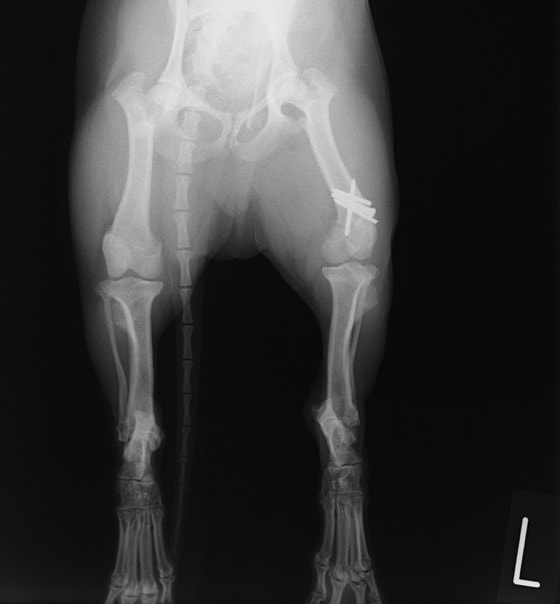

症例3:キルシュナーワイヤーのピンニングによる整復

ペルシャ猫 11ヶ月齢 雄

他院にて左大腿骨遠位の成長板骨折(salter-harrisⅠ型)が認められており、治療相談を目的として来院。当院にて、キルシュナーワイヤーを用いたピンニングにより骨折部位の整復を行いました。術後の経過は良好で、現在も経過観察中です。

術前レントゲン

術後レントゲン